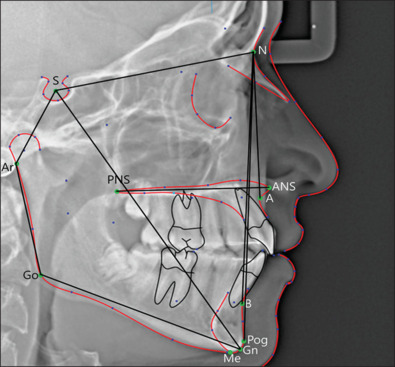

Methods and materials: A cross-sectional study was conducted on 120 6-12-year-old patients selected from the ear, nose, and throat department at Imam Al-Hussein Medical City in Karbala. Patients were classified into three groups (each = 40) based on endoscopic findings: control, grade II, and grade IV. The findings were confirmed with cephalometric radiographs. Specific cephalometric points were identified to measure sella-nasion-point A (SNA), sella-nasion-point B (SNB), point A-nasion-point B (ANB), sella-nasion-pogonion (SNPog), sella nasion plane-palatal plane (SNPP), palatal plane-mandibular plane (PPMP), sella nasion plane-mandibular plane (SNMP), saddle, articular, gonial angles, and the y-axis. Additionally, superior-posterior airway space (SPAS), posterior air way space (PAS), mandibular plane-hyoid bone (MP-H), third cervical vertebra-hyoid bone (C3-H), total anterior facial height (TAFH), total posterior facial height (TPFH), upper anterior facial height (UAFH), lower anterior facial height (LAFH), and the Jarabak ratio were measured.